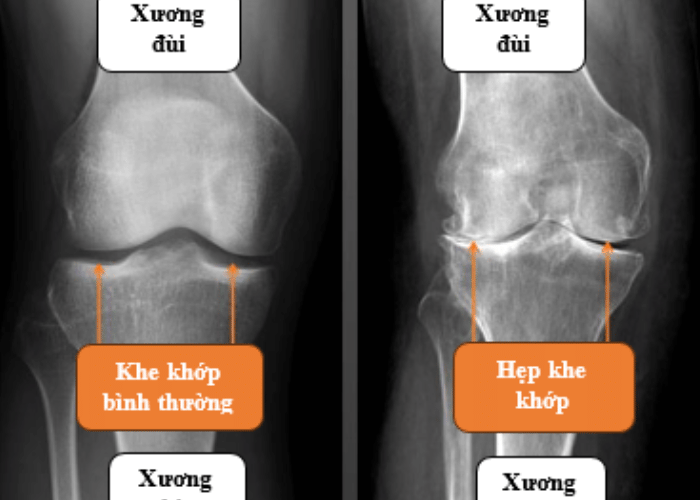

Thoái hóa khớp gối ở người già là tình trạng sụn khớp gối bị thoái hóa dần theo thời gian, làm mất đi lớp đệm bảo vệ giữa các đầu xương. Khi sụn khớp mỏng đi hoặc biến mất, các đầu xương sẽ cọ xát trực tiếp vào nhau, gây đau, viêm và hạn chế vận động.

4.2 Chẩn đoán thoái hóa khớp gối ở người già bằng phương pháp hình ảnh

Chụp X-quang giúp phát hiện hẹp khe khớp và gai xương